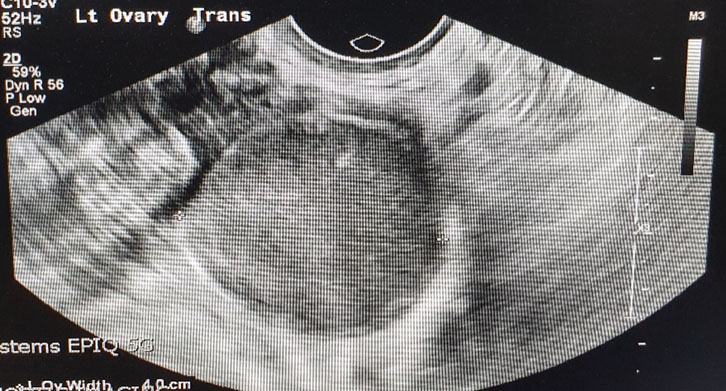

A pelvic ultrasound was done which revealed a possibility of a bicornuate uterus and a 4.4 cm mass seen within left ovary which is hypoechoic in nature which probably represent endometrioma (Figure 1). There was no free fluid noted or any adnexa mass seen. The appendix was not visualized. Due to her nonresolving abdominal pain, a CT scan of abdomen and pelvis was done. It was noted on the scan that there was an inflammatory change in the distal ileum with the appendix being slightly dilated at 6.3 mm and could suggest an early appendicitis (Figure 2 and Figure 3). Apart from the left ovary cyst there were no other abnormalities noted.

Figure 1: Ultrasound of the left ovary showing width of 4 cm.